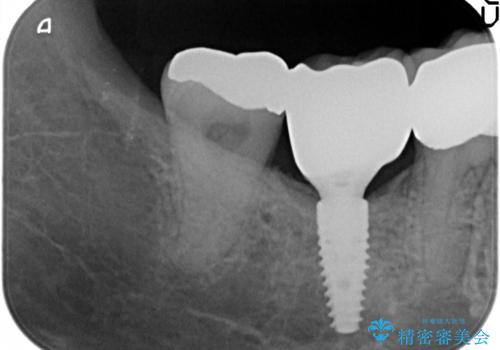

- 68.2万円 内訳(ストローマンインプラント22万円、カスタムアバットメント11万円、ジルコニアクラウン11万円、マイナーGBR5.5万円、FGG(遊離歯肉移植)11万円、静脈内鎮静5.5万円、矯正用仮歯2.2万円)(旧料金)費用は治療当時の料金となります

他院で抜歯後いらしたため、骨ができるのを待って、オペは2回法で行っております。

2回法の利点は、骨増成が確実であることと、FGGが可能で長期に安定した歯ぐきが得られることです。